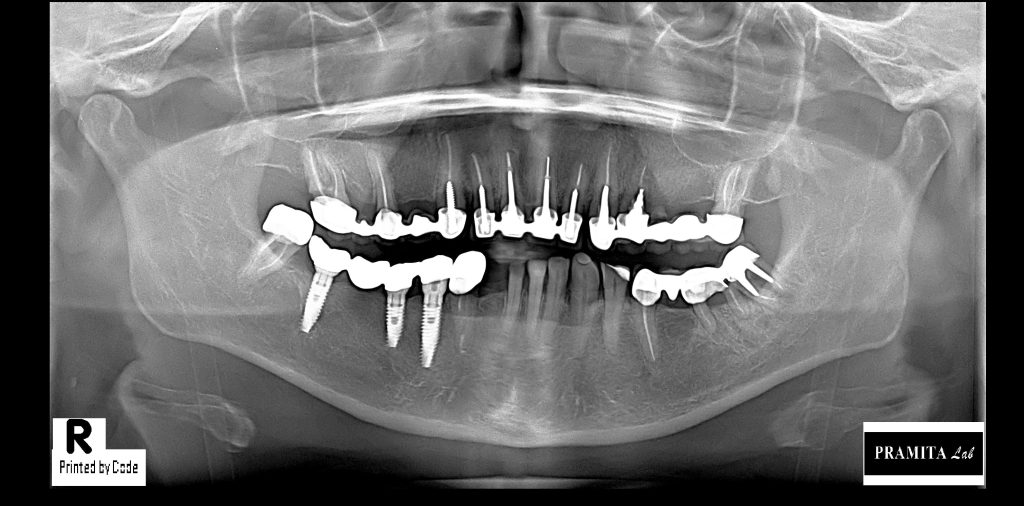

GENERAL CHECK-UP & PANORAMIX X-RAY

General dental check-up with dental photography and Panoramic X-Ray to captures a wide view of the entire mouth in a single image